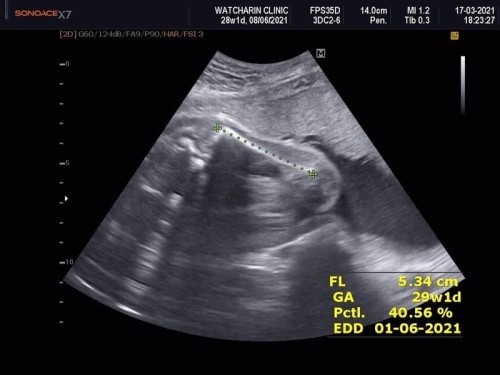

คืออายุครรภ์28สัปดาแล้วค่ะ เมื่อวานไปหาหมอตามนัด แต่พออัลตร้าซาวด์พบว่าลูกนอนขดตัวก้มหน้าหลังงอมาก ดูตรงขาวๆที่เป็นกระดูกสันหลังงอโค้งเลย และทำยังไงก็ไม่เห็นหน้า(ทุกทีจะเห็นหน้าด้านข้างหรือเกือบเห็นเต็มหน้าค่ะ) แล้วหมอก็ทัก ”ทำไมตัวงอจังเป็นอะไรรึป่าวเนี้ย” แล้วหมอก็พยายามเขย่าๆดันๆทางก้นน้อง ซึ้งก็ทำให้หลังตรงนิดนึง แต่น้องก็ยังอยู่ท่าเดิม มีใครเคยเป็นแบบนี้มั้ยคะ ไม่สบายใจเลยตอนหมอทัก มันจะเกี่ยวกับที่เรานั่งงอตัว กรือนอนหงายบ่อยหรือนอนเปลมั้ยคะ #ขอบคุณล่วงหน้านะคะ ปล.ภาพนี้คือตอนที่หมอดันๆทางฝั่งก้นน้องแล้วเส้นขาวๆที่เป็นกระดูกสันหลังตรงขึ้น แต่ตอนแรกงอโค้งเลยค่ะแต่ไม่มีภาพนั้น